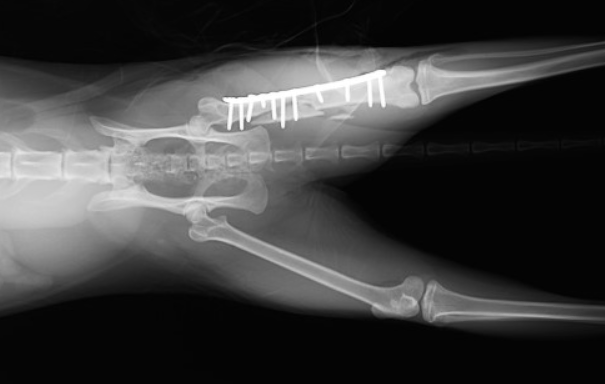

左大腿骨(後ろ足の骨)の粉砕骨折の事例です。外に出る子だったので、交通事故に遭われたのだと思います。

手術を実施し、プレートとボルトを用いて骨折整復手術を行いました。

2. 骨の固定:骨折部位を固定するためにギプス、プレートやピンを用いて損傷した骨の整復・固定する外科手術が用いられることがあります。